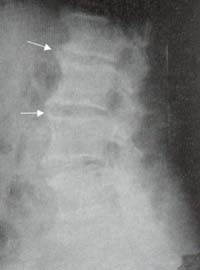

Figura 16. Se observa fenómeno del vacío del disco intervertebral entre L4 – L5,

subyacente a la esquina antero-superior de L5 (Cabeza de flecha); es signo indicativo de degeneración del disco.

Los osteofitos se desarrollan en las áreas de estrés, a algunos milímetros del borde de la vértebra,

donde el cuerpo vertebral se une al anillo cartilaginoso, no en el borde (Flecha).

Figura 19. Formaciones esteofíticas anteriores y disminución de todos los espacios intervertebrales (Flechas).